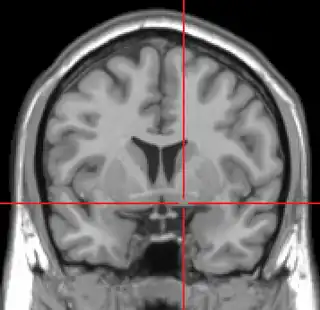

![]() Corte coronal de IRM que muestra la ubicación de la sustancia innominada con la cruz roja. | ||